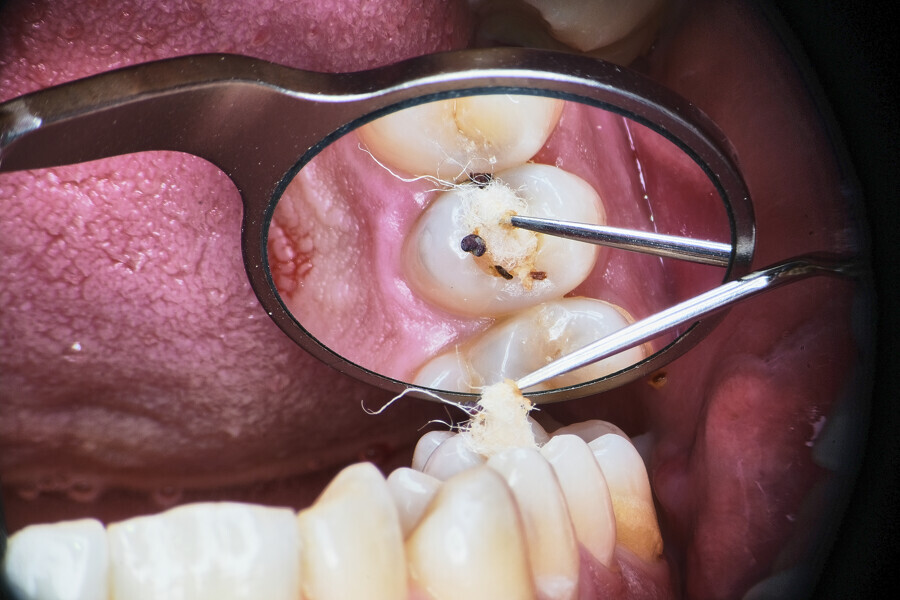

Two treatment plans were presented to the patient, non-surgical root canal retreatment and surgical root canal retreatment. After intra-oral examination, the quality of the prosthodontic treatment was found to doubtful (Fig. 24). The decision was made to remove the crown and perform non-surgical retreatment.

After local anaesthesia, the crown was cut with a high-speed handpiece (Fig. 25). The post was exposed and removed (Fig. 26 & 27). The pulp chamber and root canal orifices were examined for cracks. After inspection, a gingivectomy was performed (Fig. 28) and a dental dam (Kerr Dental) was placed (Fig. 29). The dental dam was sealed with a temporary flowable material (Fig. 30). After sealing the dental dam, the full adhesion protocol with a sixth-generation self-adhesive primer and bonding agent was performed, and the pre-endodontic build-up was created (Fig. 31). Residues of the cement and root canal filling materials were removed with a diamond-coated ultrasonic tip (Woodpecker; Fig. 32). Patency was easily established with hand files (VDW), and the canals were shaped with rotary martensitic files (Poldent) up to 40/0.04. Each step of instrumentation was performed with lubricating cream containing EDTA (VDW; Fig. 33). After each instrument, the canals were flushed with 5.25% sodium hypochlorite (Cerkamed). After reaching the final sizes of the root canals, the irrigation protocol was performed: three sequences of 5.25% sodium hypochlorite and 40.00% citric acid (Cerkamed) activated with an ultrasonic file (MANI), followed by 5.25% sodium hypochlorite activated with the ultrasonic file for approximately 10 minutes (Figs. 34 & 35). The flow of the liquid between both mesial canals was visible.

From this point of view, a novel approach of placing a tricalcium silicate-based sealer was a promising idea. The sealer was placed in the previously described manner. The premixed sealer in the plastic syringe (Meta Biomed) was placed in the mesiobuccal canal and the syringe depressed until it filled the mesiolingual canal. The distal canal was filled separately. In each canal, pistons from the previously heated gutta-percha extruder were placed and the warm gutta-percha was slightly compacted with stainless-steel hand condensers. A periapical radiograph was taken to evaluate the quality of the obturation. The bioceramic sealer was slightly extruded through the resorbed apex into the periapical area (Fig. 36). After the obturation, the chamber and orifices were cleaned (Fig. 37). A resin core with fibre posts was placed, and the temporary pink material was removed. The patient was referred to the prosthodontist for final restoration.